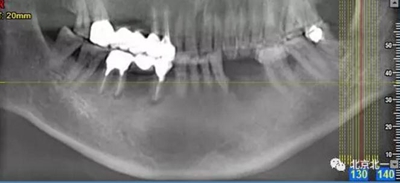

患者術(shù)前片, 最窄骨寬度僅僅3mm,34-35牙位缺失,

CBCT顯示如下圖